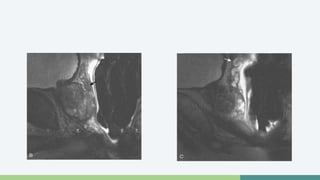

RM-Espectroscopía

• Permite la cuantificación de Metabolitos

• En próstata

• Colina

• Creatina

• Citrato

• Índice Colina+Creatina/Citrato elevado (+0.75)

• Sugestivo de proceso maligno

• En Tej Normal Hay altos niveles de Citrato, que no hay en

procesos patológicos

Ventajas

• Estatificación tumoral

• Recurrencia después del tratamiento

• Distinción ADC vs Benignos

Relación Normal vs Neoplásica

Carcinoma de Próstata extracapsular

RM-Espectroscopía • Permitela cuantificación de Metabolitos • En próstata • Colina • Creatina • Citrato • Índice Colina+Creatina/Citrato elevado (+0.75) • Sugestivo de proceso maligno • En Tej Normal Hay altos niveles de Citrato, que no hay en procesos patológicos

Ventajas • Estatificacióntumoral • Recurrencia después del tratamiento • Distinción ADC vs Benignos